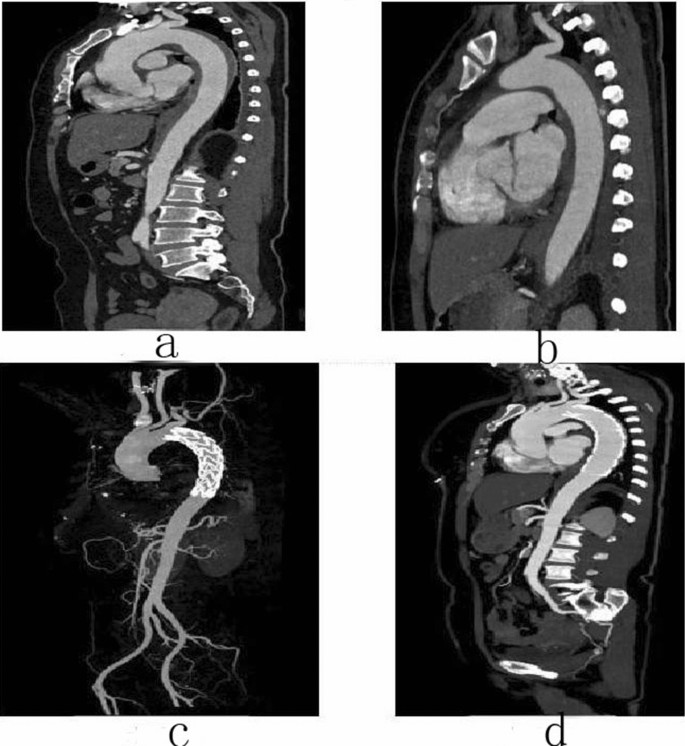

Follow-up

Female, 49 years old, admitted to hospital for “sudden tearing pain in low back for 48 h”, Diagnosis: Stanford type B aortic dissection; Treatment: IMH TEVAR treatment. CTA of the patient in different periods: (a) Admission; (b) 12 days after admission; (c) 2 days after surgery; (d) 4 months after surgery.